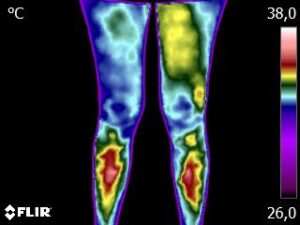

Como no caso da sequência de termogramas abaixo de um paciente feminino, 45 anos, sem comorbidades e estava em processo de reabilitação de ruptura de ligamento cruzado anterior (LCA) do joelho esquerdo na fase de liberação de atividade física. Foi realizado uma Análise Termofuncional e detectado alterações térmicas condizentes com desequilíbrio.

Estas informações foram suficientes para definir mais uma fase da reabilitação, a do reequilíbrio muscular e equilíbrio dos membros.